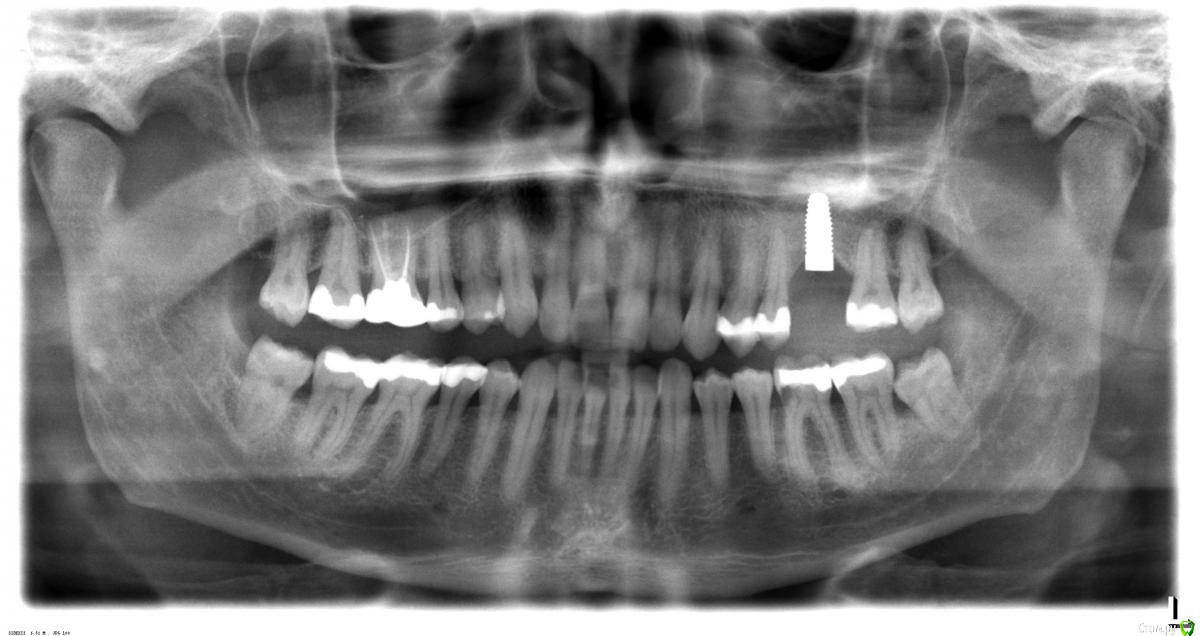

Павел45 Опубликовано 7 декабря, 2017 Поделиться Опубликовано 7 декабря, 2017 Подскажите, пожалуйста, врач сказал,что надо удалять 36 зуб, лечить нецелесообразно, корни глубокие, но очень бы не хотелось терять его, если возможно лечение. Заранее большое спасибо за советы. Ссылка на комментарий

Павел45 Опубликовано 7 декабря, 2017 Автор Поделиться Опубликовано 7 декабря, 2017 (изменено) Спасибо огромное, просто был у двух разных врачей, оба сказали удалять лучше, но у меня были сомнения, да и не беспокоит он сильно, иногда чуть побаливает и быстро проходит. Изменено 7 декабря, 2017 пользователем Павел45 Ссылка на комментарий

сирена Опубликовано 7 декабря, 2017 Поделиться Опубликовано 7 декабря, 2017 Там дело,похоже,не в длинных корнях. Ссылка на комментарий